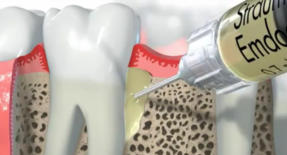

Eine erfolgreiche anerkannte Methode stellt die Behandlung mit Schmelzmatrixproteinen (Emdogain - Firma Straumann) dar.

Bestimmte Knochentaschen und bestimmte Formen von Furkationsbefall lassen sich durch spezielle parodontal-chirurgische Behandlungen regenerieren.